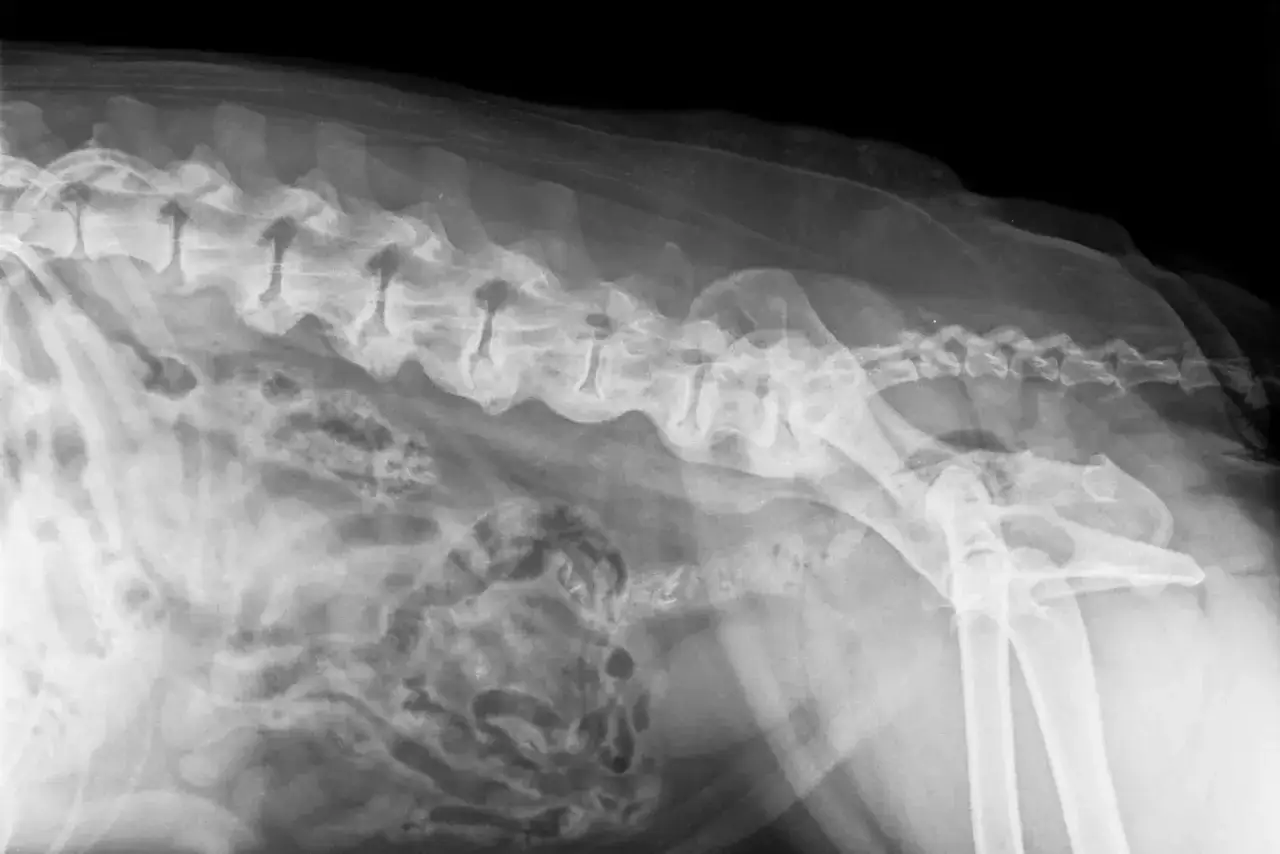

Kluczowe badanie krwi: co oznaczają wyniki T4, fT4 i TSH?

Podstawą diagnostyki niedoczynności tarczycy są badania krwi. Weterynarz zazwyczaj zleca oznaczenie poziomu kilku kluczowych hormonów:

- Całkowita tyroksyna (T4): Jest to podstawowy wskaźnik. Niskie stężenie T4 często wskazuje na problem z tarczycą.

- Wolna tyroksyna (fT4): To forma T4, która jest biologicznie aktywna i nie jest związana z białkami transportowymi. Jej poziom jest często bardziej wiarygodny niż całkowite T4, ponieważ nie jest tak wrażliwy na inne czynniki.

- Hormon tyreotropowy (TSH): Jest to hormon produkowany przez przysadkę mózgową, który stymuluje tarczycę do produkcji T4 i T3. W przypadku niedoczynności tarczycy, przysadka "widzi" niski poziom hormonów tarczycy i w odpowiedzi zwiększa produkcję TSH, próbując pobudzić tarczycę. Dlatego obniżone poziomy T4 i/lub fT4 w połączeniu z normalnym lub podwyższonym TSH są silnym wskaźnikiem niedoczynności tarczycy.

W niektórych przypadkach weterynarz może również zlecić badanie przeciwciał przeciwtarczycowych (TgAA), które potwierdzają autoimmunologiczne podłoże choroby.